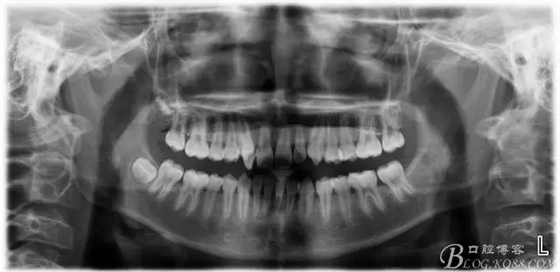

患者13歲,男性,自覺牙齒不齊要求矯正;

640.webp.jpg

640.webp (1).jpg